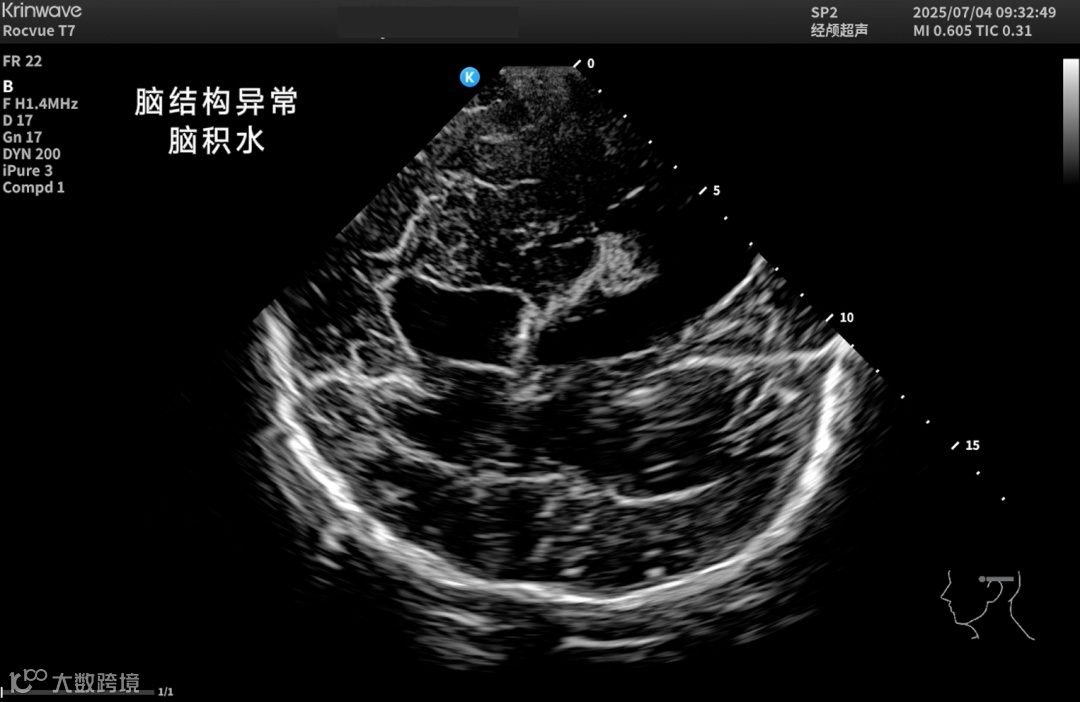

颅脑一直是超声成像的难题——

颅骨厚、衰减强、反射乱,声能传输率不足10%。

让超声在颅脑领域真正“看得见、看得清”。

● 神经重症监测

床旁实时评估颅内压、脑血流动力、脑水肿及血肿变化;